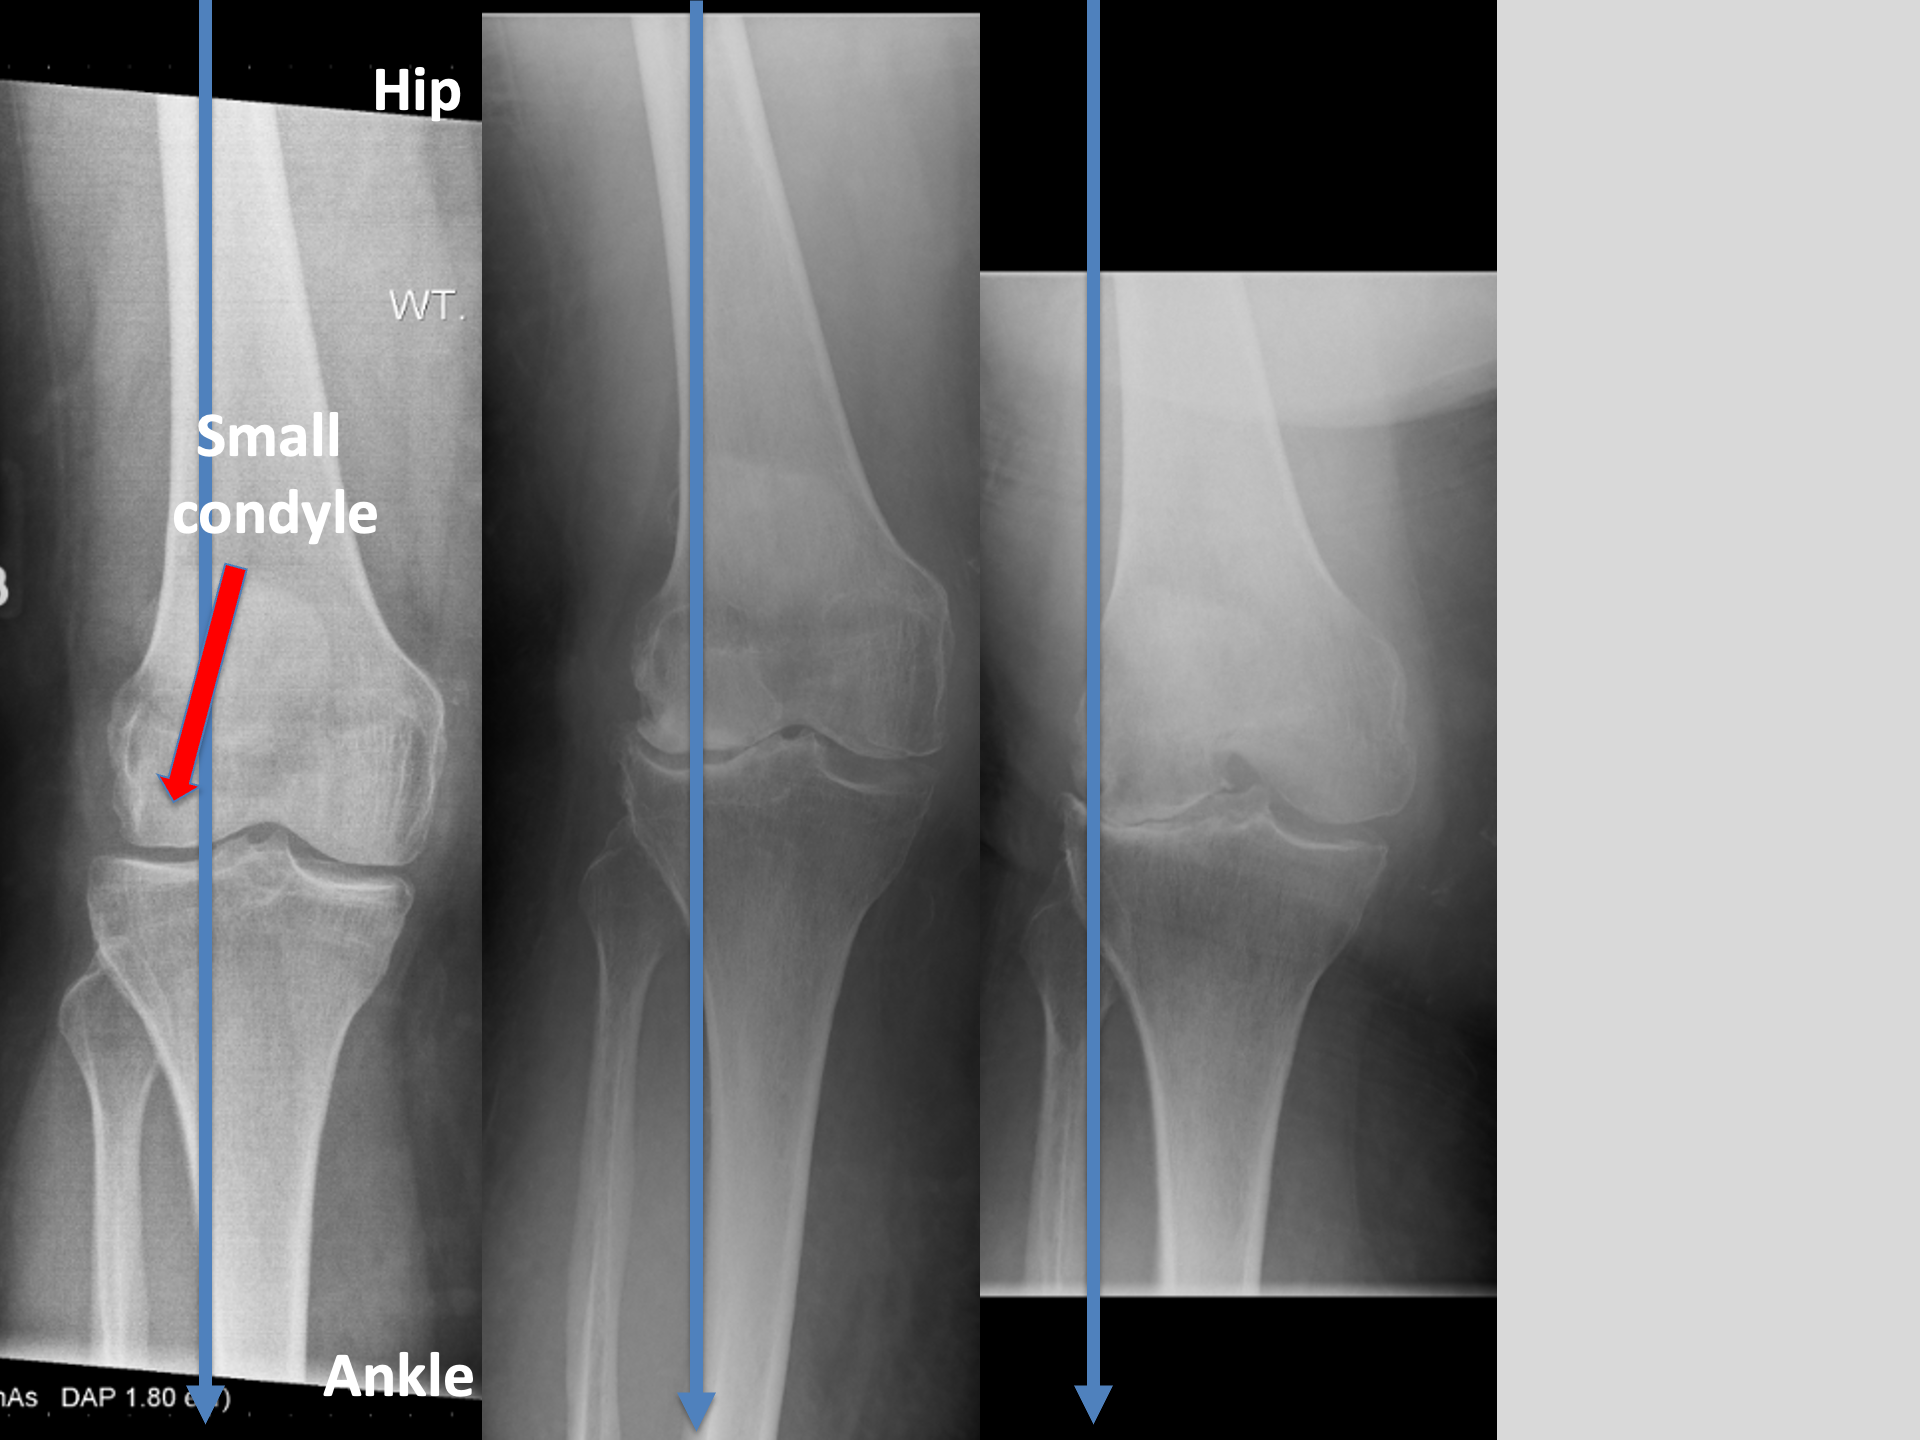

This level of deformity (see 3.)

That knee is not getting better.

AND is likely to get worse.

So, we got on with a RIGHT Total Knee Replacement.